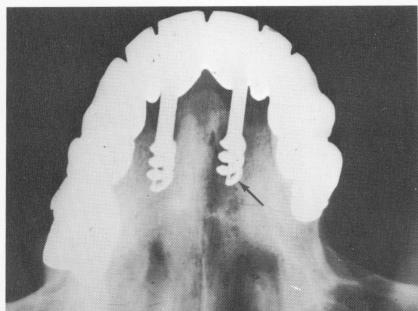

Fig. 14-11. The upper left implant perforated the labial plate of bone (arrow) during its insertion without the dentist being aware of it. A 6-month postoperative cross-sectional radiograph reveals the great amount of bone resorption caused by the perforation.

Overdrilling. Careless or overenthusiastic drilling with burs or taps can lead to perforation of the buccal, labial, lingual, or palatal plates of bone (Fig. 14-11). In the maxilla, a sinus may be entered (Fig. 14-12) or the nasal vestibulum penetrated (Fig. 14-13). In the mandible, the inferior alveolar nerve may be affected (Fig. 14-14). In addition to actually penetrating these structures and others, such as the pterygoid plexus of veins and the incisive foramen, the sites may be approached too closely, resulting in pain and other complications.

2 Upper left implant perforated labial plate of bone in maxilla